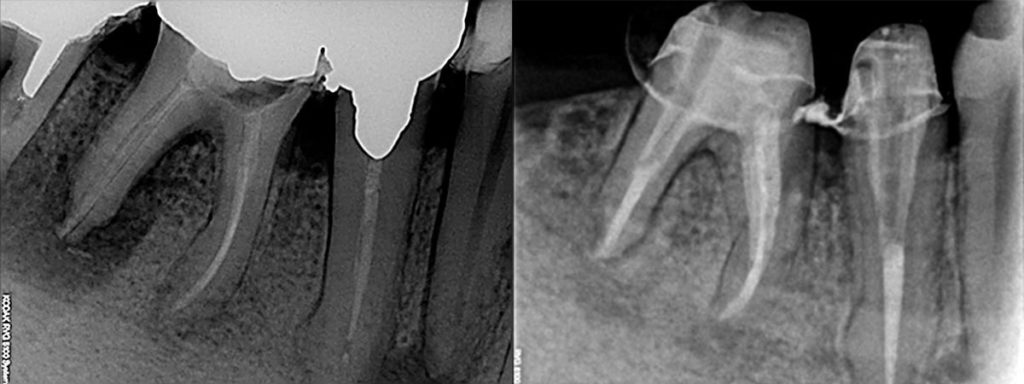

Quando un dente è stato danneggiato da una carie profonda che ha raggiunto la sua parte più interna (la camera pulpare) è necessario, per salvarlo, procedere alla rimozione del tessuto infetto rimuovendolo e disinfettando le strutture interne coinvolte.

Si continua poi effettuando l’otturazione vera e propria dei canali radicolari con un materiale inerte (guttaperca) che li occupa tridimensionalmente. Questa procedura clinica deve essere effettuata con estrema precisione.